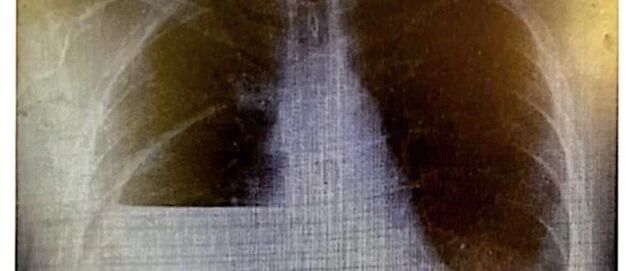

右下叶切除术后支气管残端瘘 CardiothoracicSurgery · 6 月前 |